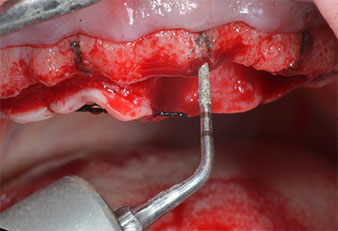

Para marcar las posiciones del implante y realizar la preparación piloto, se utilizó un inserto piezoeléctrico (Piezomed I1) con revestimiento de diamante y forma de llama (figura 3). Se tomaron precauciones para realizar movimientos hacia arriba y hacia abajo, con una potencia reducida, una irrigación completa y una baja presión (por debajo de 300 g). A continuación, se aplicó un inserto piloto (Piezomed I2A/I2P) para aumentar el diámetro inicial de 2 mm de los sitios de implante (figura 4), seguido de un inserto de 3 mm (Fig. 5).

En el caso que nos ocupa, no se utilizaron los insertos Z25P ni Z35P debido a la existencia de un hueso posterior relativamente blando, que se trató sin problemas con el I3A/I3P.

Debido al hueso relativamente duro (D2) existente en el sector anterior, los sitios de los implantes largos de 10 mm de las posiciones 11 y 21 se finalizaron con una fresa rotatoria de 4 mm de diámetro, en combinación con un contra-ángulo quirúrgico WS-75 L de W&H, el motor de implantes Implantmed de W&H y el módulo opcional Osstell ISQ de W&H. En cambio, debido a la existencia de hueso blando, los sitios posteriores se prepararon hasta un diámetro final de 3 mm utilizando el inserto Piezomed I3P. Por último, los implantes se colocaron a nivel crestal para su osteointegración durante tres meses (figuras 6-10). La prótesis existente se mantuvo sobre cuatro implantes provisionales (figura 8).